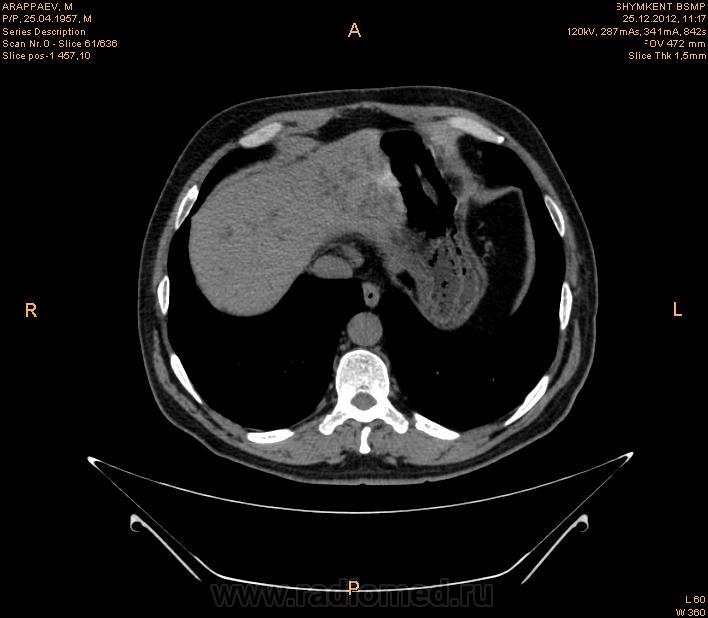

увеличение лимфатических узлов парапанкреатической зоны ,парааортальных ,в области ворот печени,вирсунгов проток расширен,внутри панкреатическую часть холедоха не проследить (возможно на срезах он резко сужен),увеличение головки и крючковидного отростка поджелудочной железы(изоинтенсивна относительно паренхимы поджелудочной железы ),с участками пониженной плотности в структуре ,с отсутствием жировой прослойки с нисходящей горизонтальной частью 12 перстной кишки,высокая вероятность инвазии как забрюшинного жира (переднее параренальное пространство). так и самого органа(рекомендуется контрастное усиление с применением негативного контраста),увеличением размеров левого надпочечника(вероятнее всего метастаз) ,изоинтенсивного исходному органу по плотности с гиподенсивными участками округлой формы в структуре ,участком повышенной плотности,линейной формы по медиальному контуру (вероятнее всего кровоизлияние ),на одном из срезов между увеличенным надпочечником и верхним полюсом правой почки определяется линейная структура изоинтенсивная ткани почки и надпочечника ?(инвазия в периренальное пространство или объемный эффект не скажу точно),гипоинтенсивные относительно печени участки округлой формы с преймущественной локализацией в левой доле (возможно мтс,рекомендуется контрастное усиление ),подковообразная почка ,слева расширенная чашечнолоханочная система ,расширенный верхний сегмент мочеточника (для более подробной информации кт с контрастом -для определения природы обструкции),расширенные внутрипеченочные желчные протоки

Подковообразная почка, с кистами слева, образование надпочечника. К тому же имеет место внутрипеченочная гипертензия. Гепатоспленомегалия. Инфильтрация парапанкреатической клетчатки (не точно). Лимфоузлы в воротах печени (неточно). Холедох я так и не разглядела, если честно.Необходимо дообследование, я думаю. КТ с внутривенным контрастированием хотя бы. Дождемся других мнений....

Спасибо большое.Я начинаюший врач КТ кабинета.Вы мне здорово помогли.Я утром заклюячение отдала не дождавший ваши мнение.Гепатоспленомегалия.Внутипеченочная гипертензия Образование правого надпочечника.Подковобразн.почка гидронефротич.трансформаций левой половины.Образование головки поджелудочн.железы? Рек -но КТ с контрастиров или МРТ исследов.